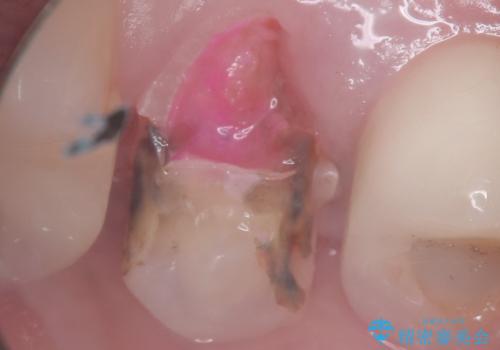

右上5番の口蓋側歯質が失われ、露出した歯質内面は軟化象牙質を除去していく過程で露髄する可能性が大きくありました。患者さんには生活歯髄療法と抜髄のどちらかになると説明し、生活歯髄療法の適応と判断し行いました。

補綴物は残存歯質量からクラウンとしました。